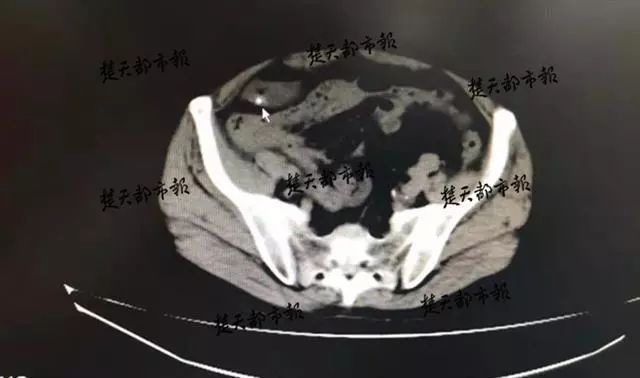

面对王豪的疑问,李先生支支吾吾,不愿多说。CT检查结果证实了王豪的判断,情况紧急之下,王豪决定立即为李先生进行剖腹探查手术。

手术中,王豪发现李先生的食管大面积损伤,腹腔已化脓感染,取出的物品更是让人大吃一惊。

“手术时,我们竟然从李先生的腹腔里取出了一条泥鳅。 ”王豪说,导致肠穿孔的物品很多,自己在病人腹腔内取出过鱼刺、枣核甚至牙签等物品, 整条的泥鳅还是第一次遇到 。 幸好李先生就医及时,否则后果不堪设想。